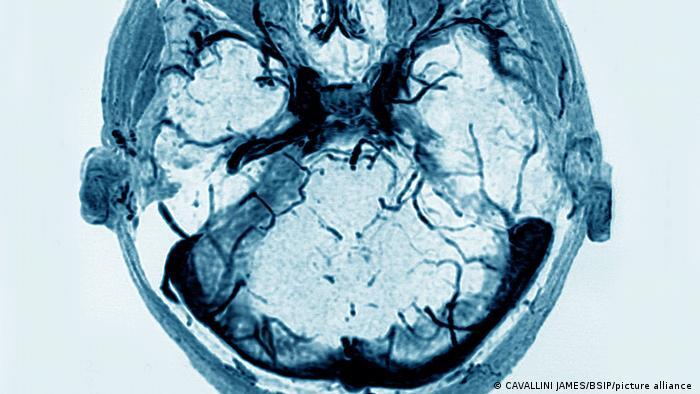

- در مورد یک میلیون و ۶۰۰ هزار دوز واکسن که تاکنون تزریق شده است در آلمان ۷ مورد ترمبوز سینوس وریدی مغزی رخ داده است. همزمان با این ترمبوز، در بیماران کمبود پلاکت خون هم مشاهده شده است. پلاکت در لخته کردن خون نقش دارد.

- دراین نوع ترمبوز، یک لخته خون در سینوسهای سیاهرگی سختشامه که وظیفه تخلیه خون از مغز را به عهده دارند را مسدود میکند.

"آلمان همانند چندین کشور دیگر، واکسیناسیون با واکسن آسترازنکا را از دوشنبه گذشته (۱۵ مارس) متوقف کرد"اگر این انسداد باعث شود که خون به راحتی تخلیه نشود، فشار در مغز افزایش یافته و باعث خونریزیهای بعدی در مغز میشود. در شدیدترین حالت این ترمبوز منجر به سکته مرگبار میشود.